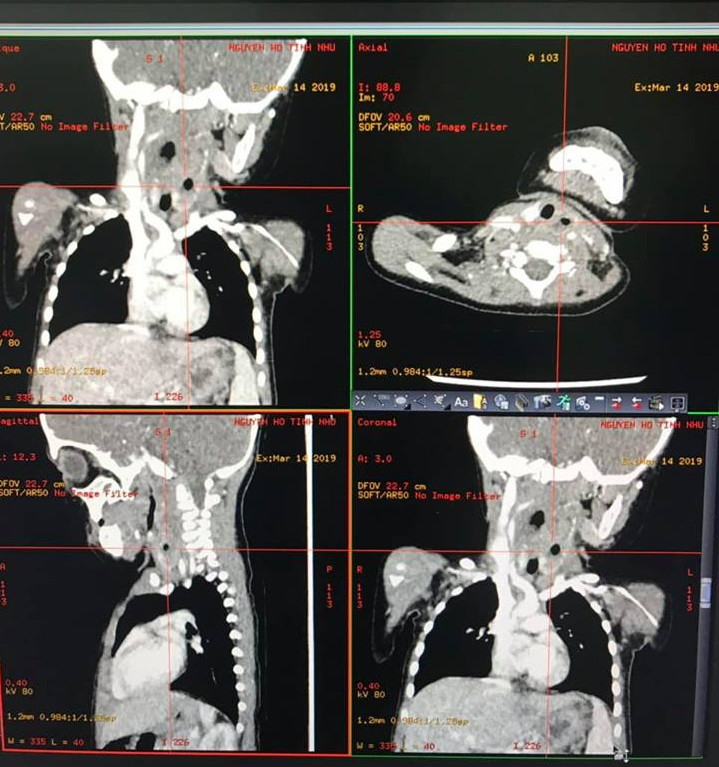

| Hình ảnh CTscan, khối u lan xuống khoang cổ sâu bên trái, giữa tuyến giáp trái và các mạch máu lớn vùng cổ, nhiều khối áp xe (Ảnh BVCC). |

Tại BV Nhi Đồng TPHCM, Bác sĩ Tai Mũi Họng ghi nhận bệnh cảnh không phù hợp với viêm họng nên tiến hành xét nghiệm máu , chụp CTscan vùng cổ.

Kết quả cho thấy bé nhiễm trùng nặng, có nhiều ổ abces lớn tụ mủ, sinh hơi ở thành sau họng, chiếm hơn 2/3 thể tích của vùng cổ. Ngay lập tức bé được chuyển vào phòng mổ cấp cứu.

BS CK2 Bạch Thiên Phương, Trưởng khoa Tai Mũi Họng, BV Nhi Đồng TPHCM cho biết: sau 3 giờ phẫu thuật tỉ mỉ, đã rạch thoát 50ml mủ xanh đục ở thành sau họng. Do khối áp xe lan xuống khoang cổ sâu bên trái, bác sĩ phải mở cạnh cổ để dẫn lưu hết mủ, nạo sạch mô viêm quanh tuyến giáp, cắt lọc phần cơ ức giáp bị hoại tử.